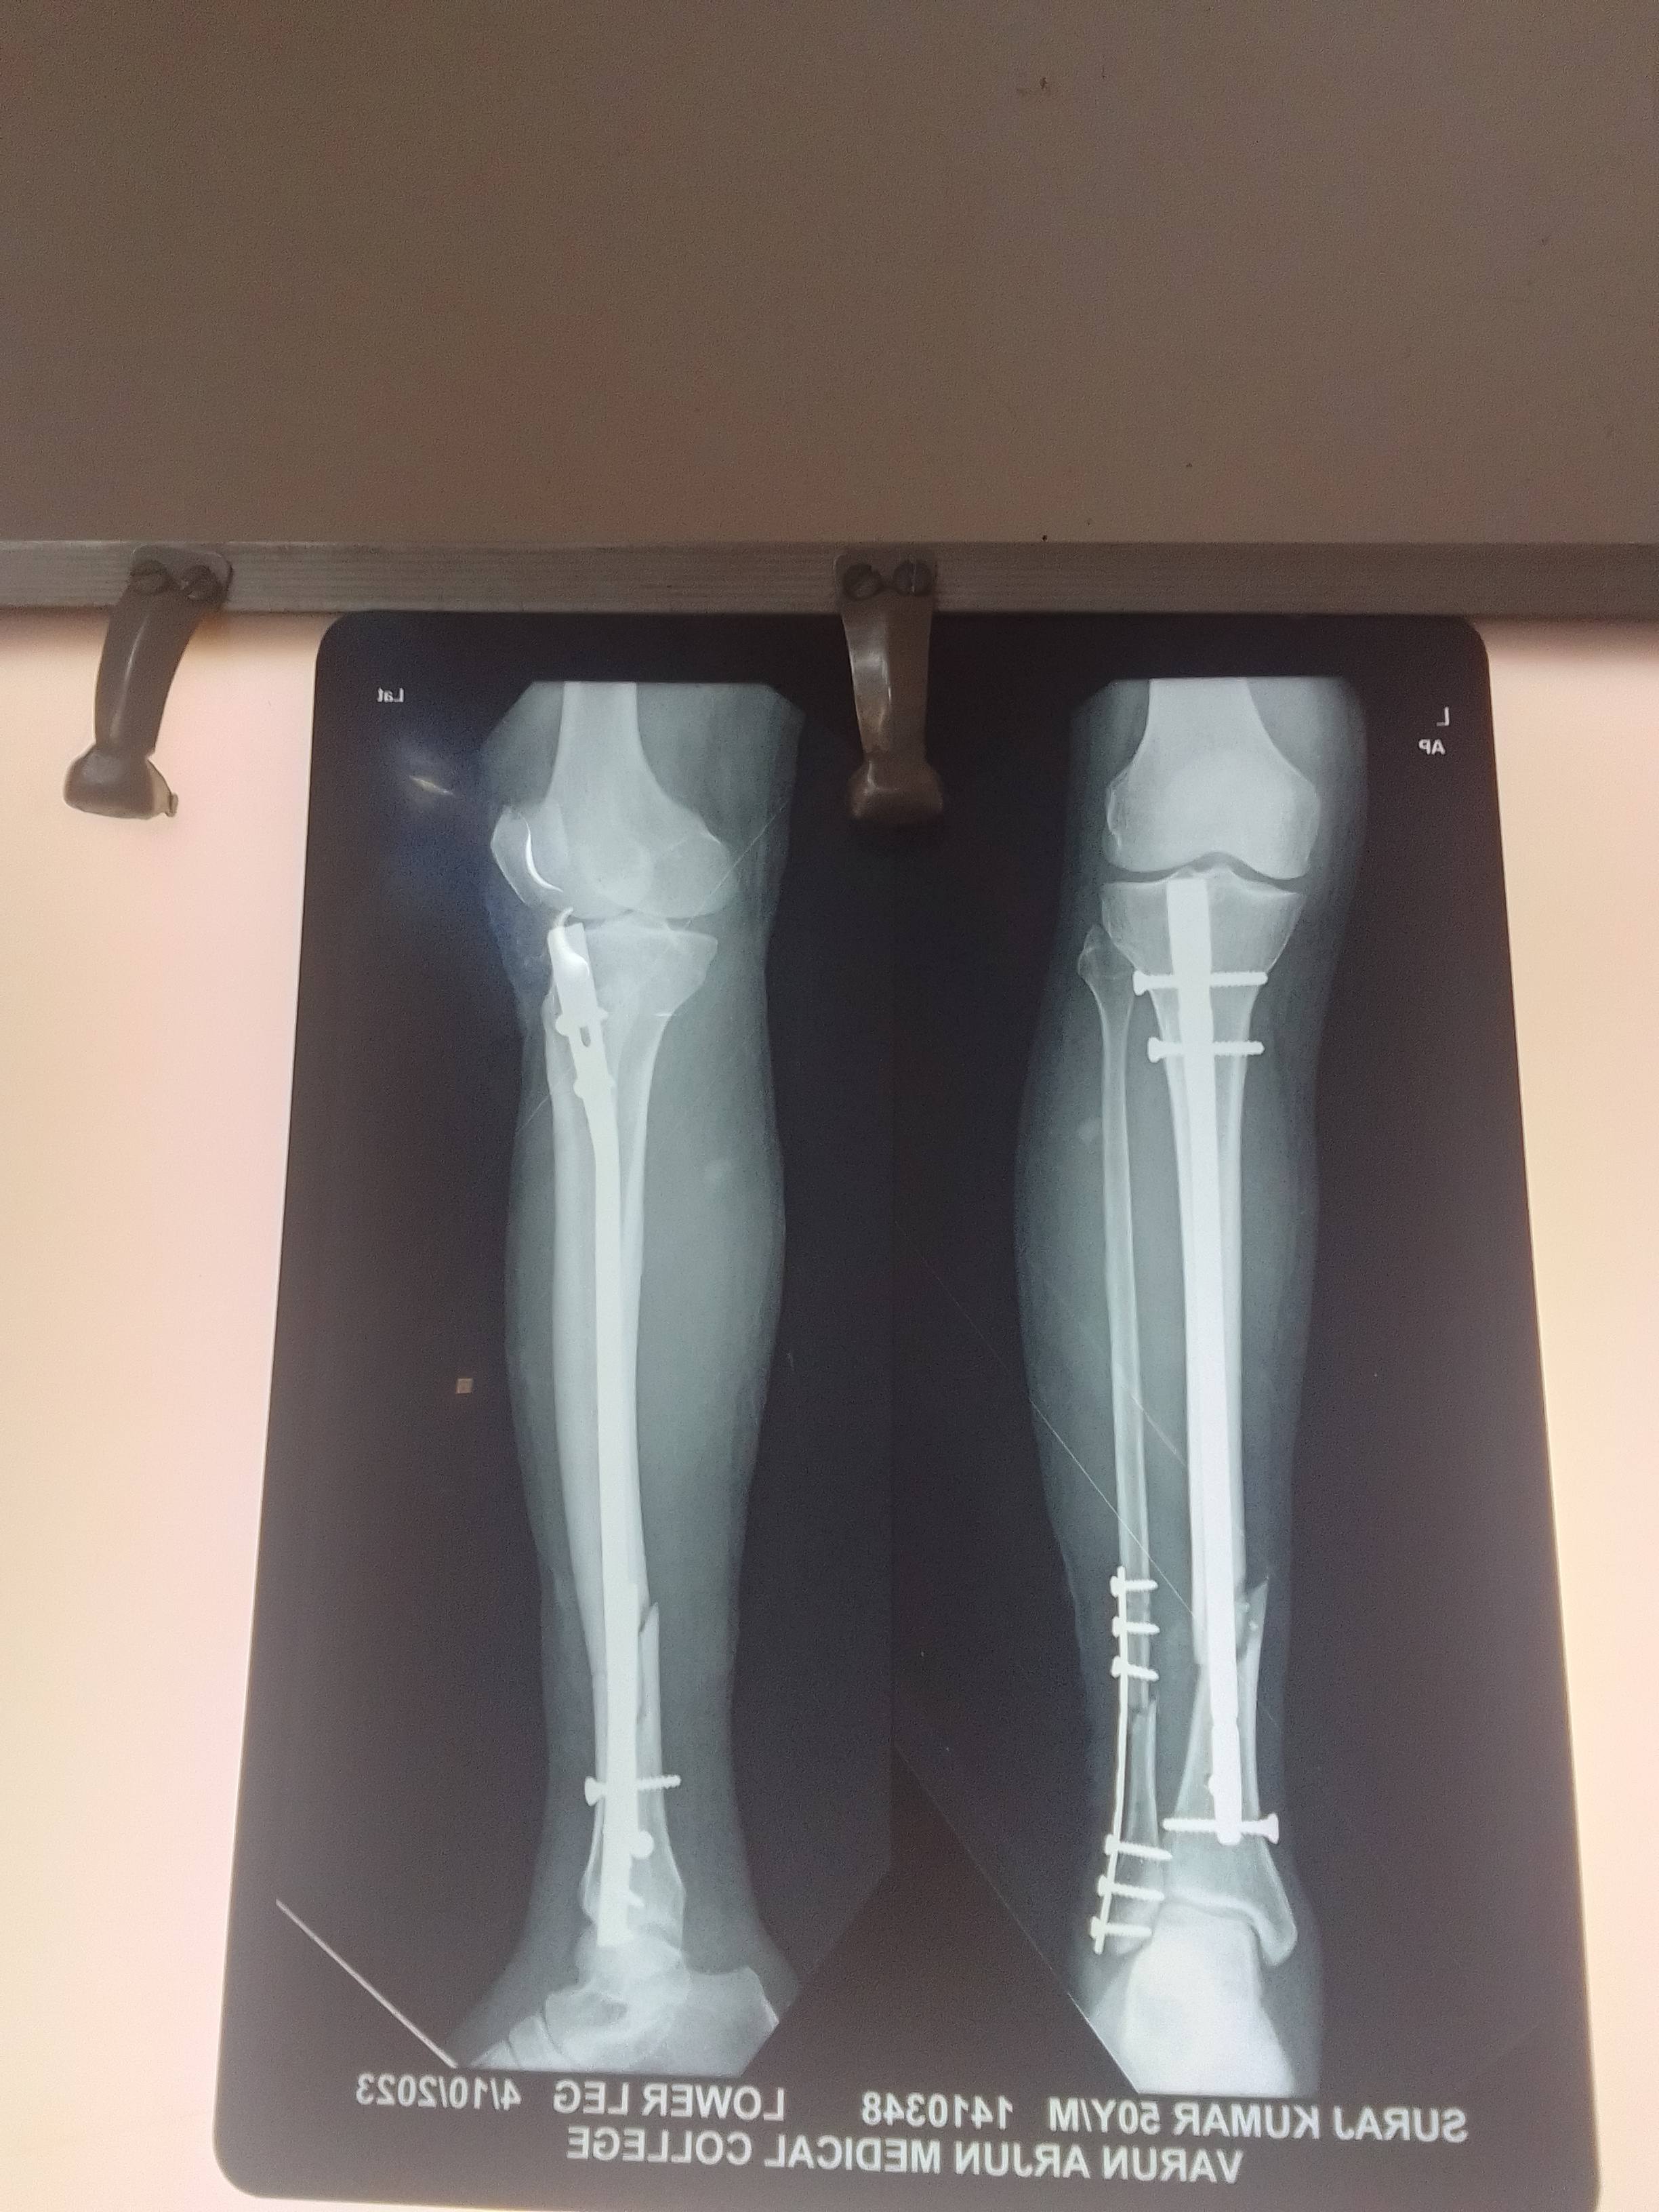

Bone Fracture